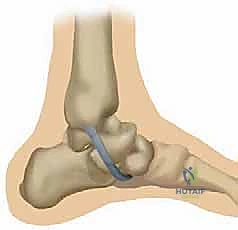

الشكل 2: تشريح مجمع الرباط الزنبركي من المنظر الأخمصي (من أسفل القدم). الجزء السفلي ينشأ من الشق بين الأوجه الأمامية والإنسية لعظم العقب. يلتصق بالسطح السفلي لمنتصف العظم الزورقي، إلى الجانب الوحشي قليلاً من اندغام الجزء العلوي الإنسي من الرباط الزنبركي. هذا الجزء يتحمل الضغط المباشر لوزن الجسم.

2. الجزء السفلي أو الأخمصي (Inferior / Plantar Calcaneonavicular Ligament):

هذا الجزء يقع في أسفل القدم ويعمل كدعامة سفلية.

* المنشأ (Origin): ينشأ من الشق الموجود بين الأوجه الأمامية والإنسية لعظم العقب (Calcaneus).

* الاندغام (Insertion): يلتصق بقوة بالسطح السفلي لمنتصف العظم الزورقي (Navicular)، إلى الجانب الوحشي (للخارج) قليلاً من مكان اندغام الجزء العلوي الإنسي.

* الوظيفة الميكانيكية: يقاوم هذا الجزء بشكل أساسي "الهجرة الأخمصية" (Plantar Flexion / Sagging) لرأس عظم الكاحل. أي أنه يمنع عظمة الكاحل من السقوط نحو الأرض.